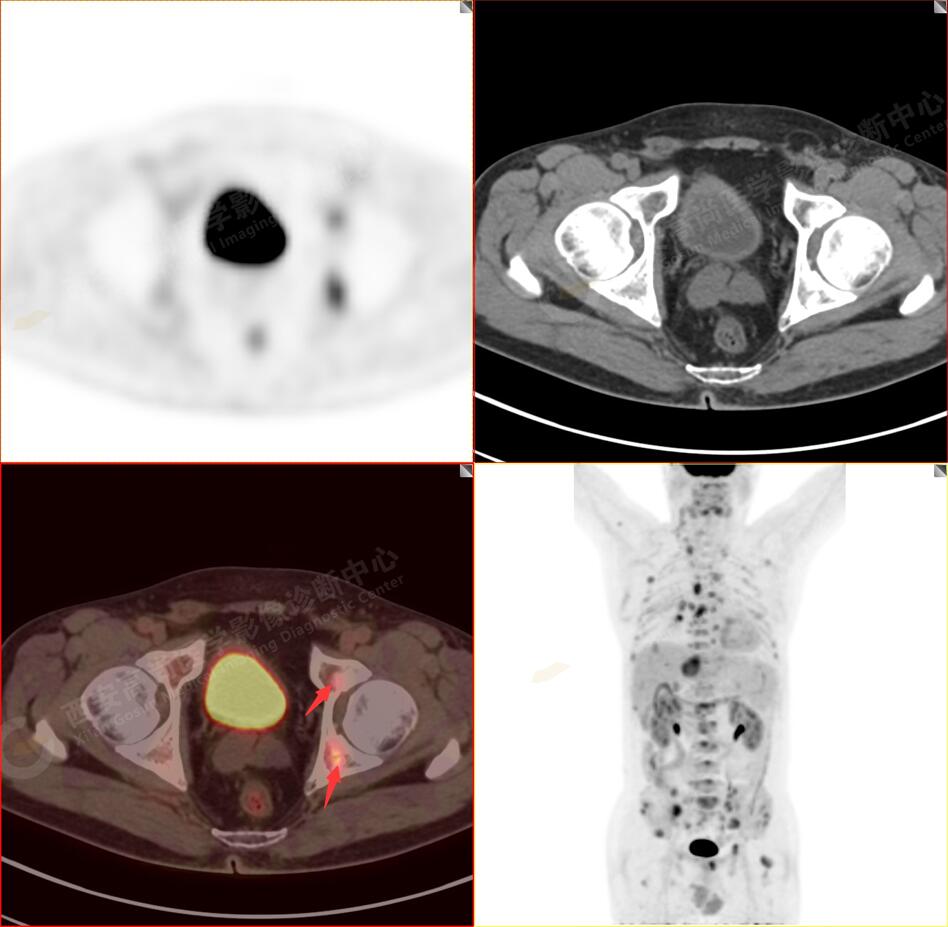

PET/CT圖像

2.以下為全身多發(fā)轉移灶

5.右側肱骨上段、左側肩胛骨、右側鎖骨胸骨端、胸骨、雙側多發(fā)肋骨、脊柱多發(fā)椎體及附件、雙側髂骨、雙側髖臼、雙側恥骨、雙側肱骨上段多發(fā)成骨性病變,呈不同程度FDG代謝異常增高,考慮為多發(fā)骨轉移瘤。